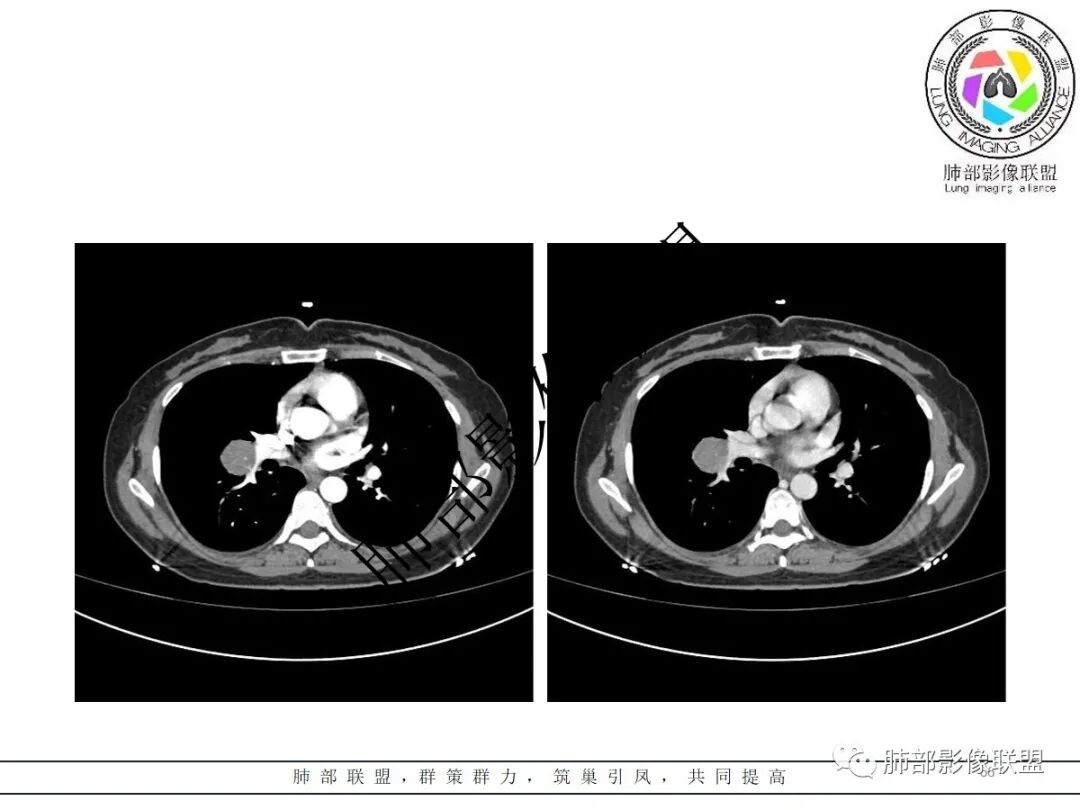

右肺门类圆形实性肿块,边缘光滑,无分叶毛刺,跨叶,推移血管,密度均匀,增强延迟强化相对明显,未见坏死及血管造影征。

2.右肺水平叶裂斜叶裂肺门交界区类椭圆形块影,表面光整,未见分叶毛刺及棘状突起,未见邻近结构牵拉。与邻近支气管无关联。

3.病灶密度均匀,未见液化坏死、钙化及脂肪低密度。轻度强化,可见纤细血管影蜿蜒穿行。右肺动脉推移变形,未见侵入或充盈缺损。

1)巨淋巴结增生症(CD)大多动脉期高强化,毕竟透明血管型占多数,本例特征不足。

3)硬化性肺细胞瘤(PSP)可以血管贴边,常常强化比较显著。

4)发生于肺表面(近脏层胸膜或叶间裂),强化不显著,可见穿行血管,与本例的符合程度是最高的。